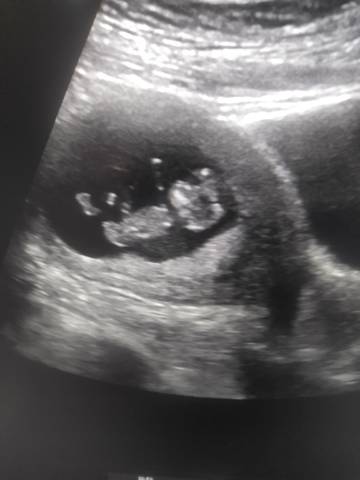

看看皮夹克还是小棉袄 好兴奋????

你好,我们都是一样觉得好奇,确实没什么依据,就个惊喜给自己吧,一切顺利!

你好。我们是判断不了男宝宝跟女宝宝的,孕期定期检查,我觉得宝宝健康就好的。祝心想事成 。